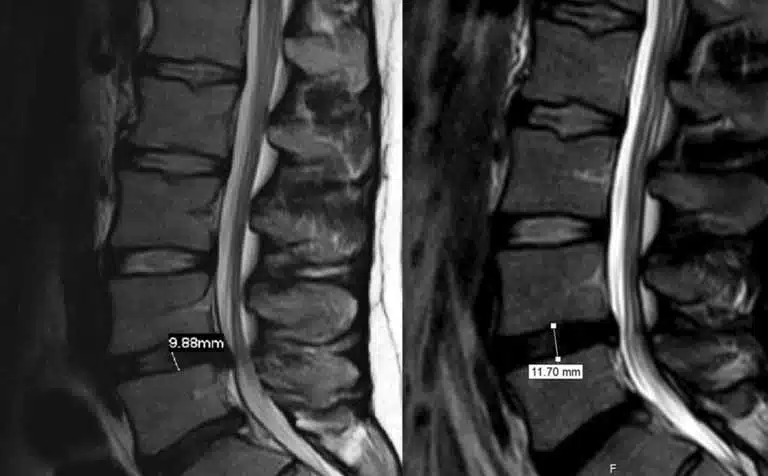

कमर की दर्द और स्पाइनल संबंधित समस्याएं आजकल बहुत से लोगों को ग्रसित कर रही हैं, और इसमें L4-L5 और L5-S1 disc bulge एक सामान्य समस्या है। इस लेख में, हम इस समस्या के संबंधित उपचार की बात करेंगे, और कैसे इस स्थिति को सुधारने के लिए विभिन्न उपायों का उल्लेख करेंगे।

इस रूपरेखा में, हमने L4-L5 और L5-S1 disc bulge treatment in hindi? के इलाज के कुछ सामान्य उपायों का उल्लेख किया है।